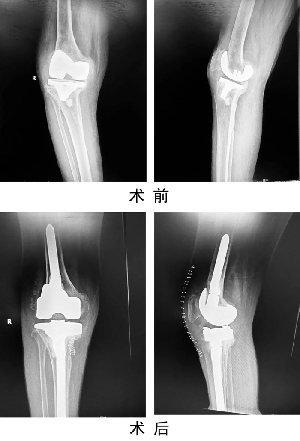

關(guān)節(jié)運動醫(yī)學二科蘇長征團隊,在我院首次成功開展人工膝關(guān)節(jié)假體周圍感染一期翻修術(shù),標志著我院關(guān)節(jié)置換手術(shù)技術(shù)又上新臺階。患者,女,69歲,因“右膝人工關(guān)節(jié)置換術(shù)后6年,疼痛伴活動受限1年”入住關(guān)節(jié)運動醫(yī)學二科。術(shù)前X線示右膝人工關(guān)節(jié)假體松動,感染指標檢查:C反應蛋白80mg/L,血沉20mm/h,關(guān)節(jié)穿刺培養(yǎng)提示表皮